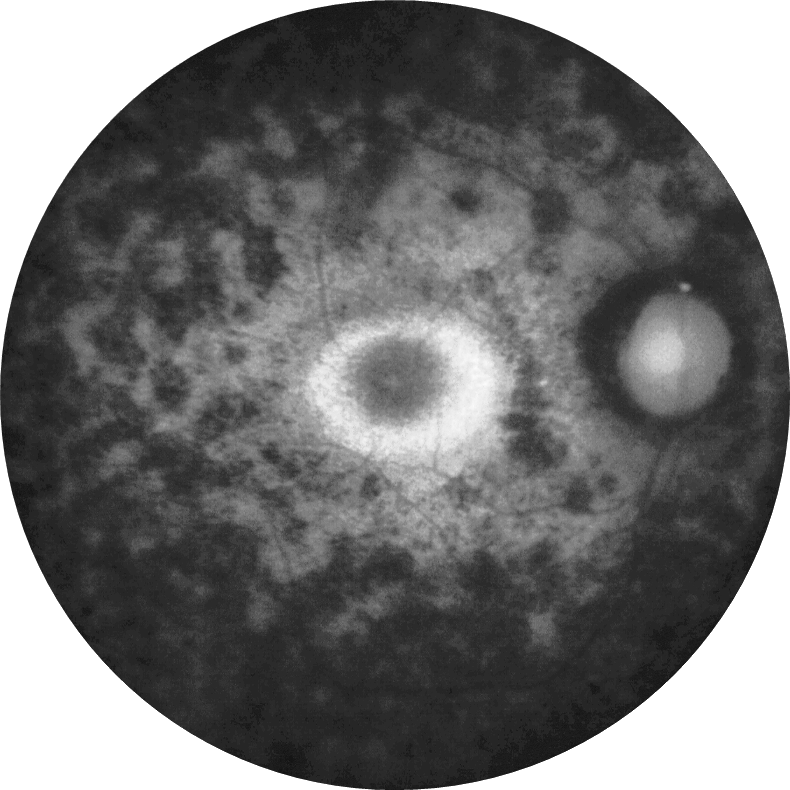

2026 Şubat Ayın Sorusu

Sağ gözde beş gündür artan görme azlığı olan 30 yaşındaki kadın hastanın renkli ...